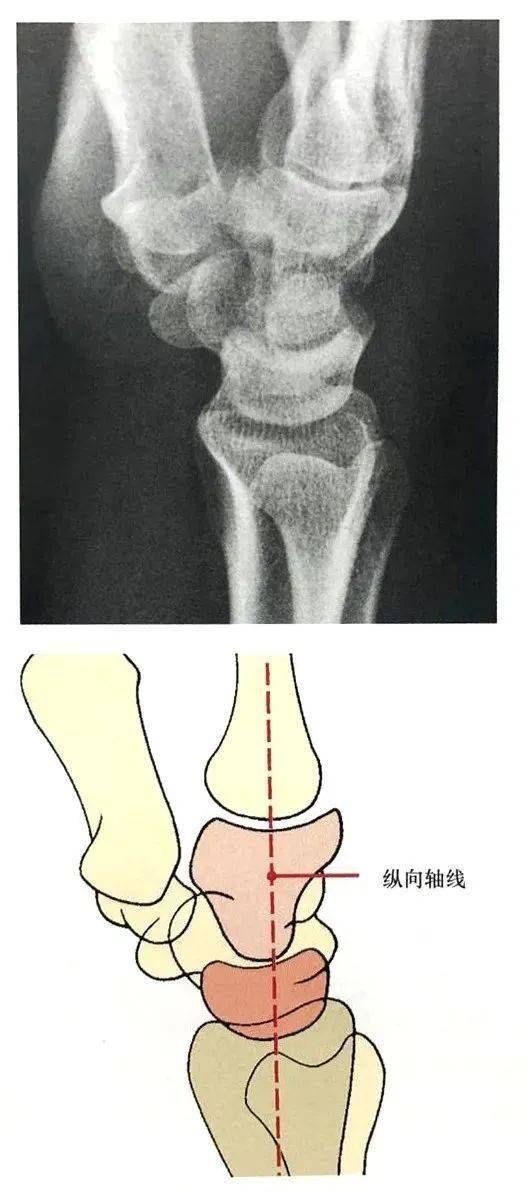

腕关节脱位及其x片阅读技巧

影像解剖丨腕关节大全--解剖,骨折,脱位,值得收藏!